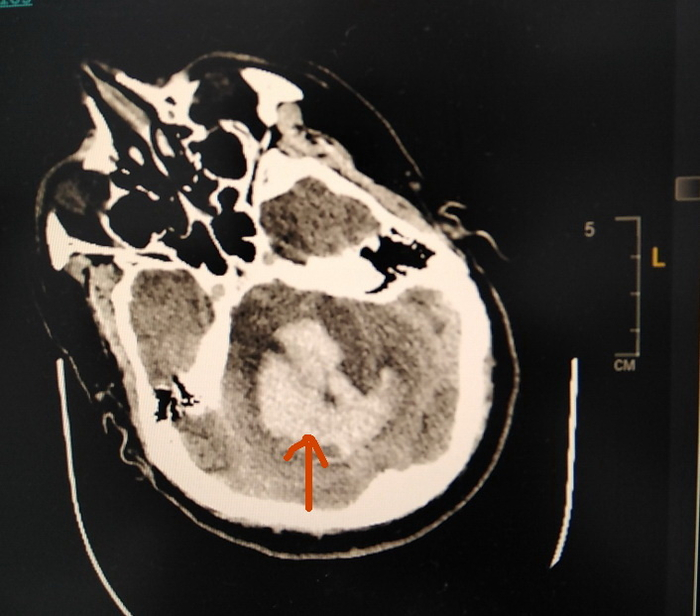

45-летний пациент был госпитализирован в нашу реанимацию в связи с утратой сознания. Мы уже никогда не узнаем, лечился ли он от повышенного давления или нет, но история болезни такая. Проснувшись утром, он измерил давление, и обнаружил, что верхний показатель превышают 200 мм рт. ст. Вызвал скорую помощь, в присутствии бригады ощутил интенсивную головную боль, и вскоре потерял сознание. На компьютерной томографии головы картина просто удручающая…

Нейрохирургическая операция в таком случае бесполезна, перспективы плохие.